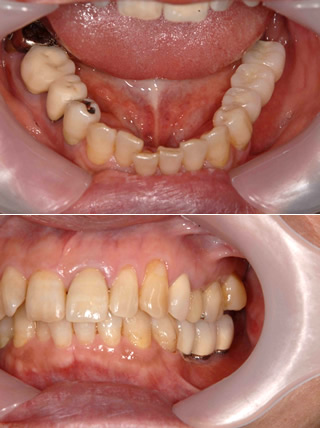

インプラント治療例